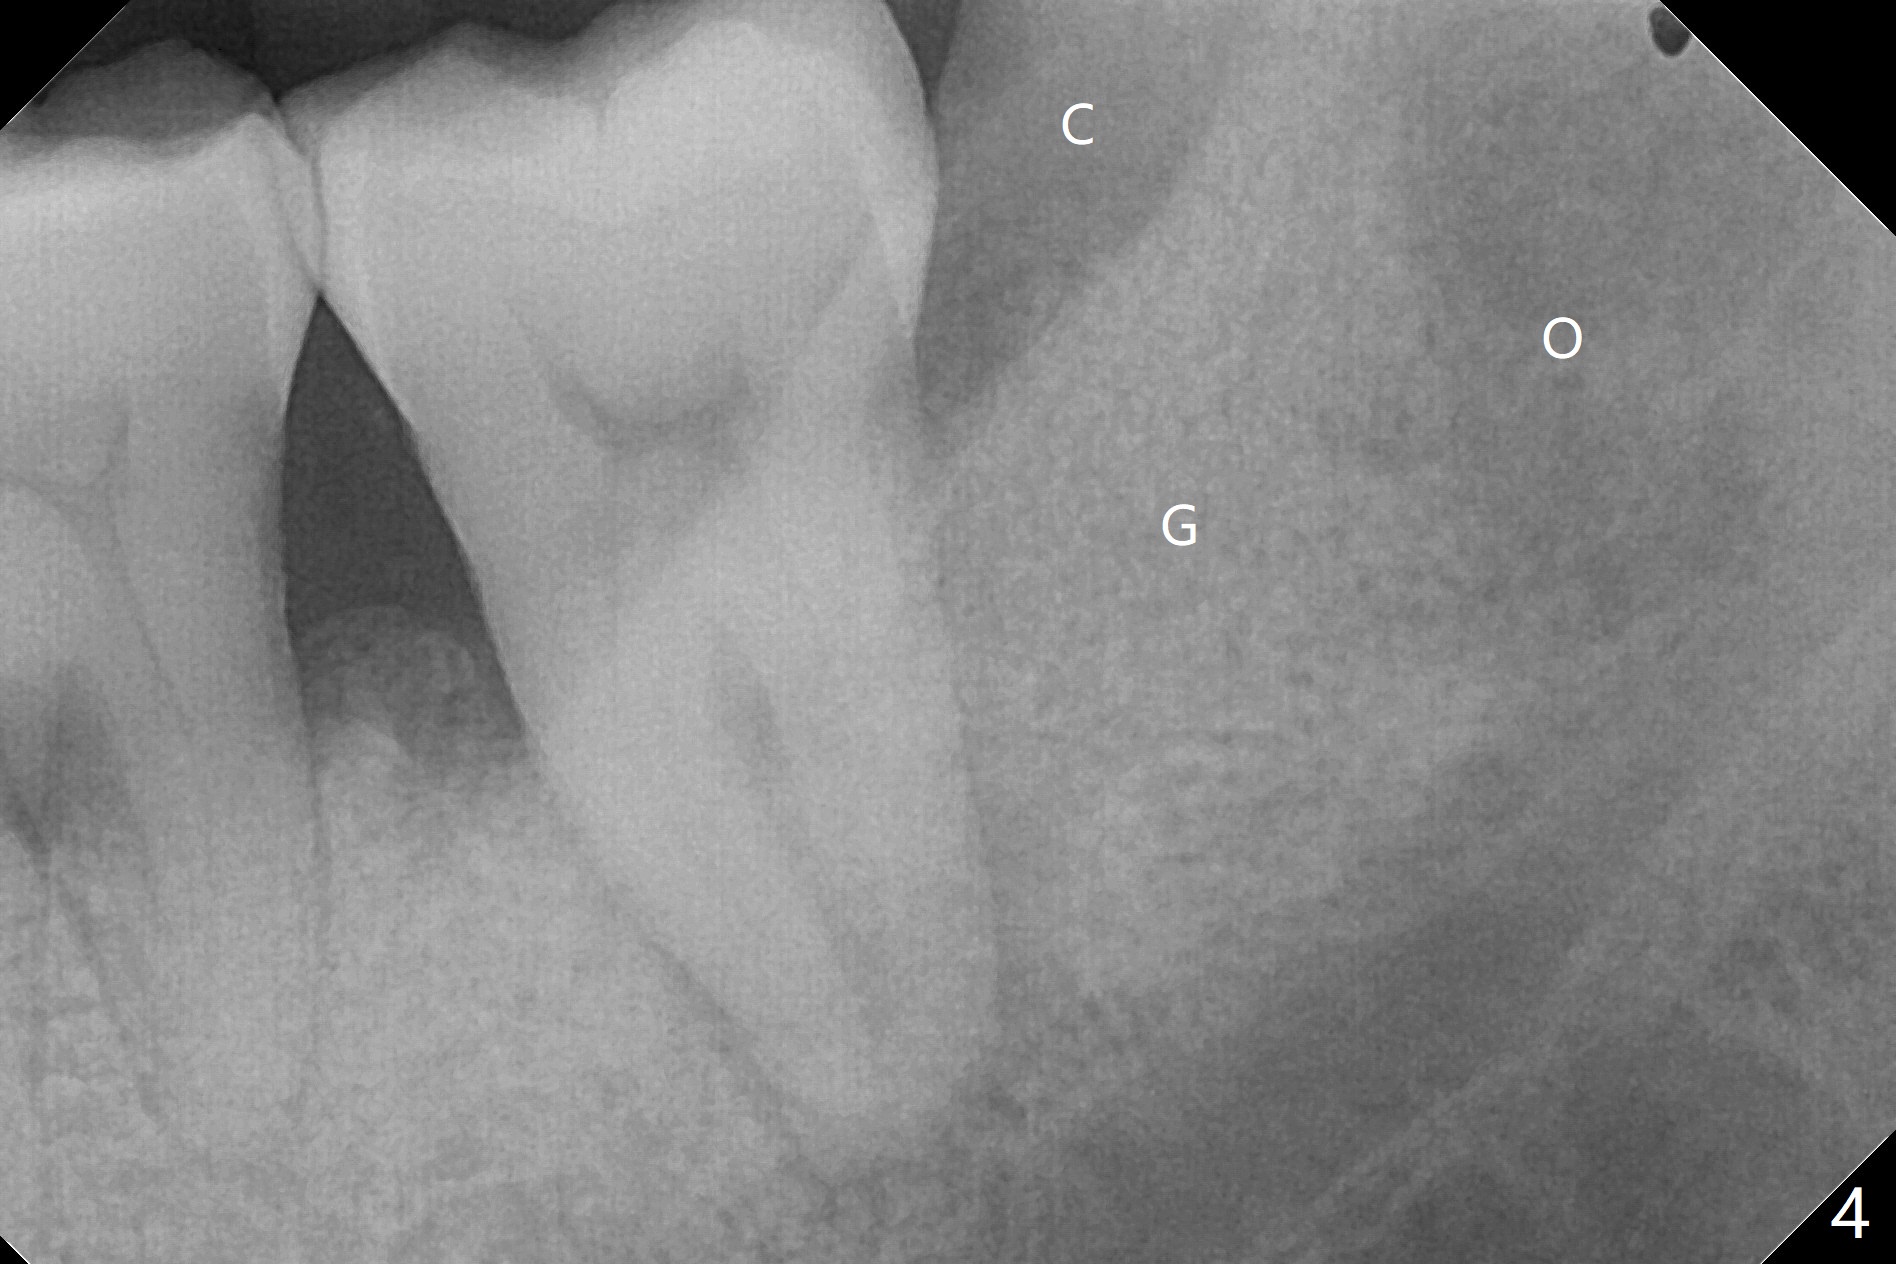

54岁男,吸烟,血糖略微升高,牙周炎,左下智齿疼痛,要求拔除(图一)。由于18号牙近中也有骨质吸收,预后不佳,所以拔除智齿后准备放置胶原塞,防止干槽症。左侧深洗后,发现智齿位于第二磨牙颊侧远中(图二),所以在第二磨牙近中做斜行切口(图三),万一伤口裂开,骨粉流失不会太多。智齿拔除后,发现第二磨牙骨质吸收严重,觉得植骨必要,但是没有时间制备PRF。使用GEM21S与皮质骨骨粉调袢。由于缺损巨大,17号牙牙槽窝远中塞入骨胶原塞(图四:O (Osteogen Plug)),18远中和颊侧放置骨粉(G),骨粉上面放置胶原塞(相当膜的作用),然后缝合。